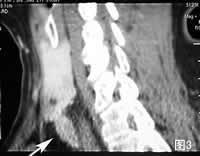

CT(图1:平扫;图2:冠状多层重组;图3:矢状多层重组):示甲状腺左叶(*)后下方长圆形软组织密度结节(箭号),中度增强,界限清楚。